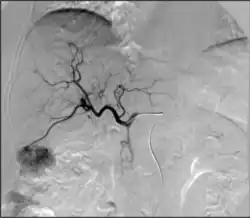

• Chemoembolization: Combined injection of chemotherapy and embolic agents into the arterial blood supply of a tumor, with the goal of both local administration of chemotherapy, slowing "washout" of the chemotherapy drug, and also decreasing tumor arterial supply

• Radioembolization: Combined injection of radioactive glass or plastic beads and embolic agents into the arterial blood supply of a tumor, with the goal of both local administration of radiotherapy, slowing "washout" of the radioactive substance, and also decreasing tumor arterial supply

• Transarterial embolization (TAE)/bland embolization: Injection of embolic material (microparticles, alcohol, glue) through a catheter into the arteries feeding a tumor to completely occlude the tumor's blood supply and cause cell death. The most common indication is for treatment of unresectable liver cancer (hepatocellular carcinoma).[64]

• Transarterial chemoembolization (TACE): Injection of a chemotherapy agent often with microparticles through a catheter into arteries feeding a tumor that both delivers chemotherapy and blocks the blood supply to the tumor to cause cell death[65]

TACE

• Can be performed in different ways:

• Conventional transarterial chemoembolization (cTACE): Injection of lipiodol with high dose chemotherapy with or without microparticles directly into the tumor-feeding arteries.[66]

• Drug eluting bead transarterial chemoembolization (DEB-TACE): delivery of microparticles that are themselves loaded with the chemotherapy agent—typically doxorubicin or irinotecan.

• Selective internal radiation therapy (also known as SIRT or Y-90 radioembolization): Injection of small beads loaded with a radioactive isotope, yittrium-90 (Y-90), into blood vessels feeding a tumor to deliver a lethal dose of radiation to cause cell death.[67] Can be performed in a segmental (radiation segmentectomy) or a lobar (radiation lobectomy) fashion. Radiation lobectomy is commonly performed with the goal of inducing growth of the non-diseased lobe in order to have adequate liver function necessary to undergo surgical resection.

• Liver cancer: primary liver tumors such as hepatocellular carcinoma or cholangiocarcinoma and liver metastases are often treated by procedures such as transarterial chemoembolization (TACE), Selective internal radiation therapy (SIRT/Y-90 radioembolization), portal vein embolization, transarterial/bland embolization, or image guided ablation (RFA, MWA, IRE, cryoablation)[69]